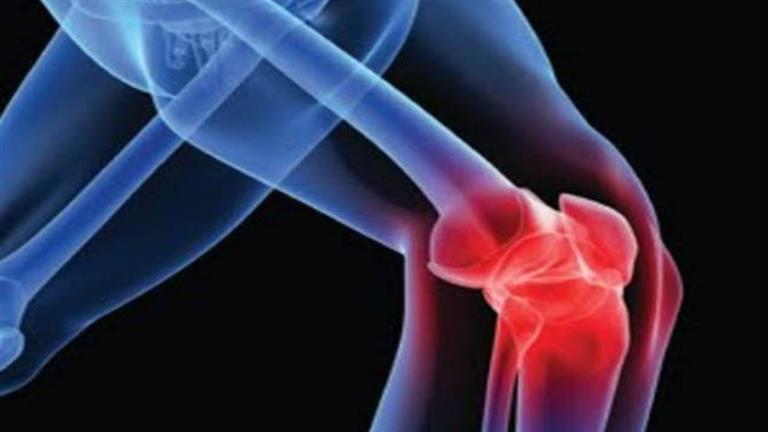

من الشائع أن نعتقد أن عظامنا صلبة وغير متغيرة، لكنها تتكون من أنسجة حية تتغير باستمرار، كل عام، يتم استبدال 15% من العمود الفقري و5% من الوركين بعظام جديدة من خلال عملية تسمى إعادة البناء، كل 10 سنوات، يتم إعادة بناء الهيكل العظمي بالكامل.

ومع التقدم في السن والإصابة ببعض الأمراض المزمنة، يمكن أن تفقد العظام تدريجيا بشكل أسرع من استبدالها، ما يزيد من خطر انخفاض كثافة العظام وهشاشة العظام، ما قد يؤدي إلى كسور في الورك والعمود الفقري والمعصم، بحسب nypost.

من الذي يجب أن يقلق بشأن هشاشة العظام؟

يجب أن تكون صحة العظام محل اهتمام من الجميع، وخاصة في منتصف العمر وما بعده، وتشير التقديرات إلى أن 10.2 مليون شخص في سن الخمسين وما فوق يعانون من هشاشة العظام، وحوالي 43.3 مليون شخص آخر يعانون من انخفاض كتلة العظام، ما يعرضك لخطر الإصابة بهشاشة العظام.

تتعرض النساء في سن اليأس وانقطاع الطمث للخطر بشكل خاص بسبب انخفاض مستويات هرمون الاستروجين بشكل طبيعي، هذا الهرمون رئيسي في عملية إعادة تشكيل العظام، عندما تتقلب مستوياته أثناء سن اليأس ثم تنخفض بعد انقطاع الطمث، يتسارع فقدان العظام.

كما أن الأشخاص الذين يعانون من اضطرابات هرمونية، مثل فرط نشاط الغدة الدرقية وفرط نشاط الغدة جار الدرقية، ومتلازمة كوشينغ، وهي حالة صماء، لديهم أيضًا فرصة أكبر للإصابة بهشاشة العظام.

ولكن أي شخص يعاني من حالة متجذرة في الالتهاب المزمن يكون معرضًا لخطر متزايد للإصابة بهشاشة العظام ويجب أيضًا إجراء الفحص، وتشمل هذه الحالات التصلب المتعدد ومرض باركنسون والتهاب المفاصل الروماتويدي والصدفي ومرض التهاب الأمعاء وأمراض الرئة المزمنة وأمراض الجلد مثل الإكزيما الشديدة وأمراض المناعة الذاتية للجلد مثل الصدفية.

لماذا يعد الاهتمام بصحة العظام أمرا مهما؟

من المهم أن ندرك أن سلامة الهيكل العظمي تحدد غالبًا نوعية حياتنا في السبعينيات والثمانينيات والتسعينيات من العمر، ولكن بمجرد أن تبدأ في كسر العظام، فقد يؤثر ذلك على نوعية حياتنا لأنه قد يتسبب في فقدان استقلاليتنا.

ما هي العلاقة بين الالتهاب المزمن وهشاشة العظام؟

علاج الأمراض الالتهابية، مثل الاستخدام طويل الأمد لأدوية الكورتيكوستيرويد أو بعض الأدوية المضادة للصرع، يمكن أن يؤدي إلى تسريع فقدان العظام، ولكن العملية الالتهابية نفسها يمكن أن تؤدي إلى فقدان العظام، حتى قبل بدء العلاج.

يمكن للأمراض الالتهابية أن تؤثر على صحة العظام لأنها تنتج وفرة من السيتوكينات المؤيدة للالتهابات، تعمل هذه البروتينات الصغيرة التي ينتجها الجهاز المناعي على زيادة معدل الخلايا التي تتحلل العظام من خلال عملية إعادة البناء.